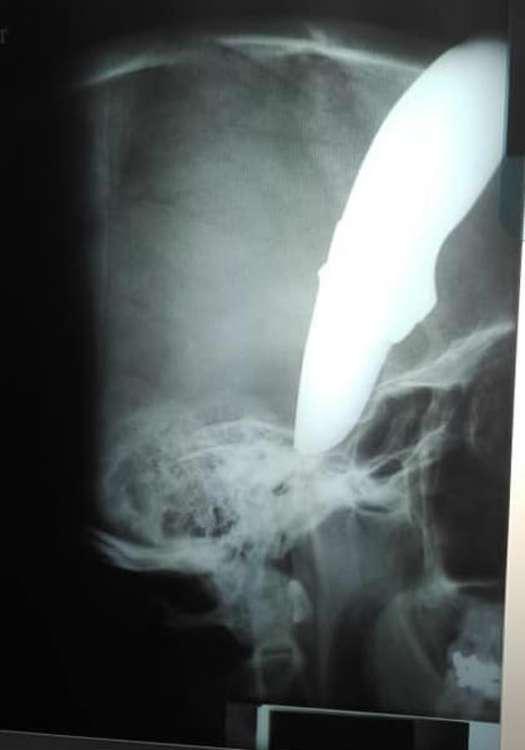

Αφού αντιστάθηκε και ακολούθησε μάχη, ο ένας εκ των επιτιθέμενων του κάρφωσε ένα μαχαίρι στο κεφάλι!

Ο 34χρονος Γουέιν δεν τα έχασε και αφού κατάφερε να τους ξεφύγει συνέχισε για 800 μέτρα με το ποδήλατο μέχρι να φτάσει στον γιατρό προκειμένου να σώσει την ζωή του με το μαχαίρι των 15 εκατοστών καρφωμένο στο κρανίο του!

Ο Σον Γουέιν μπήκε στο χειρουργείο και η κατάστασή του σύμφωνα με τους γιατρούς είναι σταθερή. Όπως είπε ένας από τους γιατρούς, ο 34χρονος ήταν πολύ τυχερός παρότι το μαχαίρι είχε καρφωθεί πολύ βαθιά στο κρανίο του.

Οι φωτογραφίες του Γουέιν έκαναν τον γύρο του διαδικτύου και είναι πραγματικά σοκαριστικές. Όπως εντυπωσιακό είναι και το πόσο ψύχραιμος δείχνει.